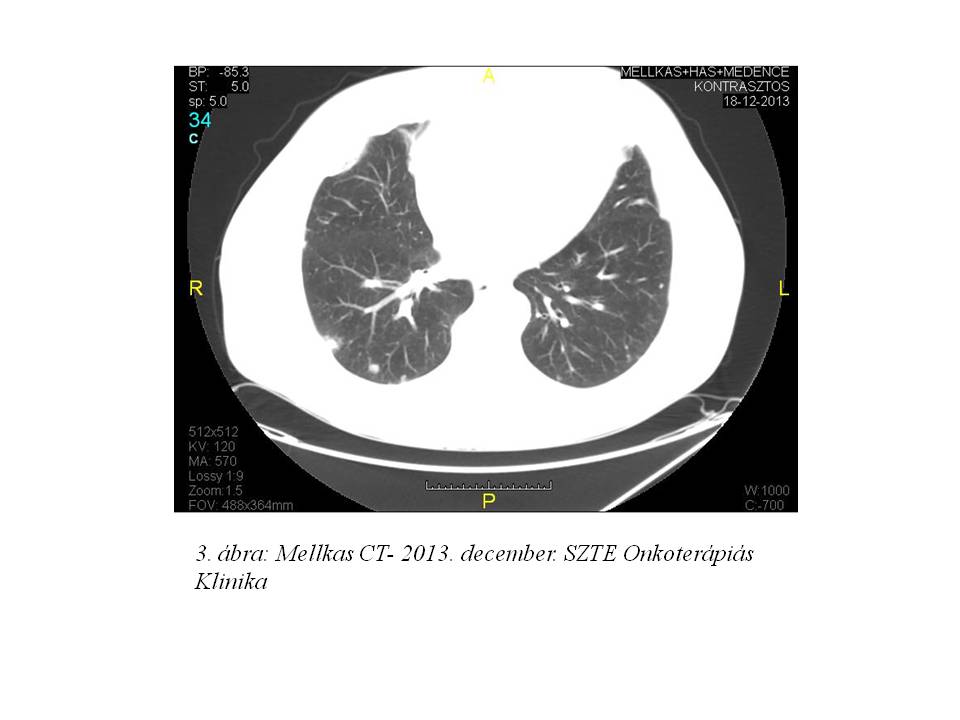

Az első staging mellkasi CT vizsgálat 3 hónap után részleges regressziót írt le (3. ábra), majd további javulást figyelhettünk meg (4. ábra, 5. ábra).

Az esetünket öszefoglalva: betegünk eddig 17 ciklus sorafenib kezelést kapott. Teljes dózisú terápia mellett csak grade I-es, jól tolerálható mellékhatások jelentkeztek. A tüdő áttétek valamint a mediastinalis és hilusi lymphadenomegalia részleges regressziója már 3 hónap kezelés után bekövetkezett.